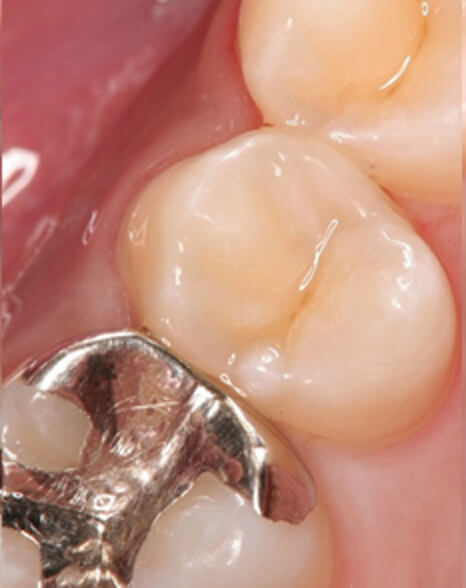

ダイレクトボンディング症例4

虫歯が進行した部分のみを除去

術前

患者さんはダイレクトボンディング法を希望されたため虫歯が進行した部分のみを除去しました(削る量は最小限で済むため歯にやさしい治療です)

ダイレクトボンディング 治療後

術後

ダイレクトボンディング治療後